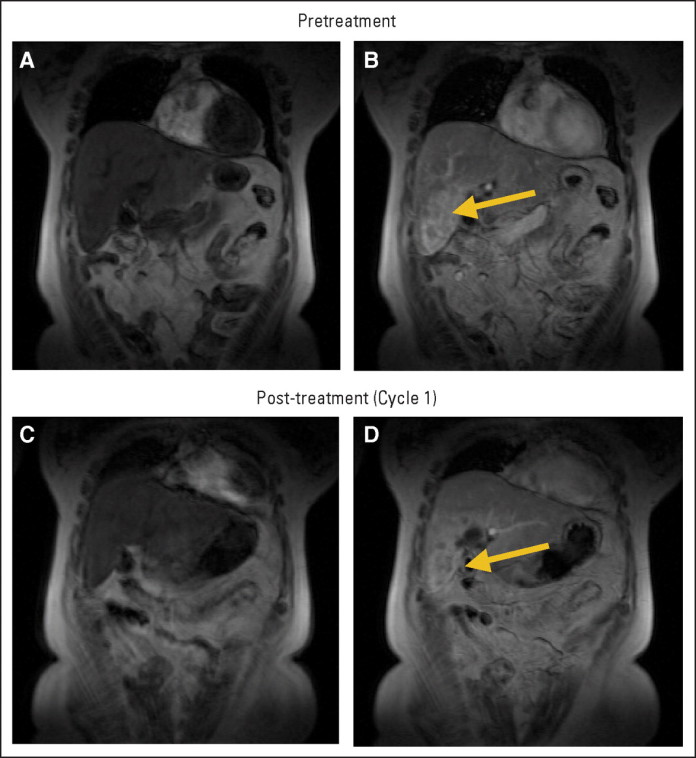

El ensayo investigó el uso de ramucirumab , un anticuerpo desarrollado para el tratamiento de tumores sólidos que se dirige a factor de crecimiento vascular endotelial receptor – 2 ( VEGFR – 2 ) , un receptor clave en el proceso de angiogénesis . Se demostró que ramucirumab inhibe eficazmente un grupo de proteínas que estimulan la angiogénesis , un proceso fisiológico mediante el cual los nuevos vasos sanguíneos se forman a partir de vasos preexistentes , que desempeña un papel clave en el crecimiento del tumor maligno . Estas proteínas inducen el crecimiento capilar en el tumor , el suministro de los nutrientes que necesita .

El ensayo clínico se llevó a cabo en 355 pacientes con cáncer gástrico avanzado , 238 de los cuales recibieron tratamiento con ramucirumab , mientras que 117 recibieron placebo. Todos los pacientes también recibieron mejor atención de apoyo . El grupo de tratamiento ramucirumab mostró una mejora de la supervivencia media ( 5,2 meses frente a 3,8 meses en el otro grupo ) , un mejor control del tumor y una reducción notable en el riesgo de progresión de la enfermedad o la muerte . Después de seis meses de tratamiento con ramucirumab , la supervivencia del paciente en este grupo fue 40 % , mientras que la respuesta al tratamiento estándar era notablemente inferior (por debajo de 20 % ) .

Dr. Josep Tabernero , jefe del Servicio de Oncología Médica del Hospital Universitario Vall d’Hebron , Director del Vall d’Hebron Instituto de Oncología ( VHIO ) , y uno de los co- autores de este estudio , confirmó que » los resultados de este estudio son importantes por varias razones . en primer lugar, el estudio revive la idea de que la inhibición del proceso de la angiogénesis juega un papel importante en el cáncer gástrico , que puede ser utilizado para lograr resultados en estos pacientes . esto es importante porque los estudios anteriores con el fármaco bevacizumab – que inhibe el factor de crecimiento endotelial vascular ( VEGF) – . no mostraron ningún beneficio significativo de esta enfermedad segundo lugar, los resultados del estudio abren nuevas vías para los pacientes con cáncer gástrico , que ofrece más opciones de tratamiento en tercer lugar , los nuevos estudios que combinan ramucirumab con medicamentos de quimioterapia. en el cáncer gástrico se nos hace muy optimista sobre el resultado de estas combinaciones , debido a las sinergias entre las drogas. Esto es probable que cambie la manera en que tratamos el cáncer gástrico en el futuro. »